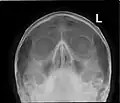

![]() Lateral projection of the paranasal sinuses | |

Paranasal sinuses are a group of four paired air-filled spaces that surround the nasal cavity.[1] The maxillary sinuses are located under the eyes; the frontal sinuses are above the eyes; the ethmoidal sinuses are between the eyes, and the sphenoidal sinuses are behind the eyes. The sinuses are named for the facial bones and sphenoid bone in which they are located. The role of the sinuses is still debated.

- The maxillary sinuses, the largest of the paranasal sinuses, are under the eyes, in the maxillary bones (open in the back of the semilunar hiatus of the nose). They are innervated by the maxillary nerve (CN V2).[2]

- The frontal sinuses, superior to the eyes, in the frontal bone, which forms the hard part of the forehead. They are innervated by the ophthalmic nerve (CN V1).[2]

- The ethmoidal sinuses, which are formed from several discrete air cells within the ethmoid bone between the nose and the eyes. They are innervated by the ethmoidal nerves, which branch from the nasociliary nerve of the ophthalmic nerve (CN V1).

- The sphenoidal sinuses, in the sphenoid bone. They are innervated by the ophthalmic and maxillary nerve (CN V1 and V2).[2]